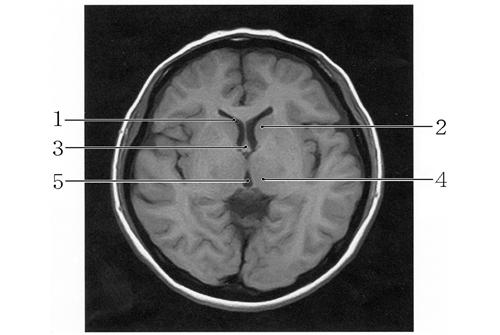

頭部MRIを示す。正しいのはどれか。2つ選べ。

1

第3脳室

2

尾状核

3

松果体

4

視 床

5

第4脳室